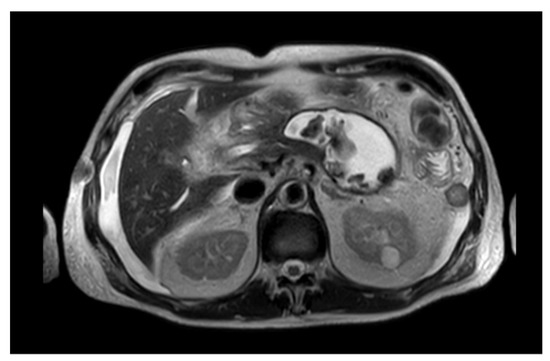

- Dhaka, N.; Samanta, J.; Kochhar, S.; Kalra, N.; Appasani, S.; Manrai, M.; Kochhar, R. Pancreatic Fluid Collections: What Is the Ideal Imaging Technique? World J. Gastroenterol. 2015, 21, 13403–13410. [Google Scholar] [CrossRef] [PubMed]

- Brizi, M.G.; Perillo, F.; Cannone, F.; Tuzza, L.; Manfredi, R. The Role of Imaging in Acute Pancreatitis. La Radiologia Medica 2021, 126, 1017–1029. [Google Scholar] [CrossRef]